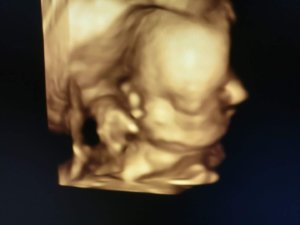

4D babamozi

Ezek a képek nem a babamoziban készültek, hanem az egyik nőgyógyászati vizsgálaton, mobiltelefonnal. Ezeken jobban látszódik a babák arca, mint a babamoziból.

Összességében született pár cuki kép, és az egész fel lett véve videóra is. B magzat jógapózban volt végig, mégpedig olyanban, amire élő ember szerintem nem képes: mindkét lába a fejéhez volt behúzva teljesen, így az arcát nem is láttuk igazán.

Mindent összevetve az emlék miatt megérte.